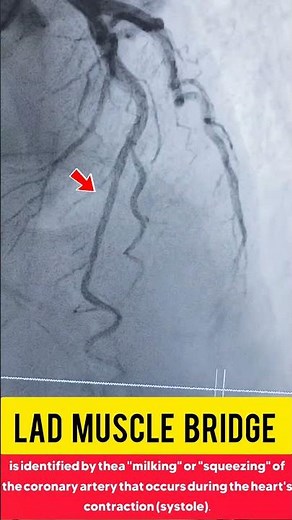

LAD Muscle Bridge - Muscle Bridge

Myocardial Bridge - Myocardial Bridge